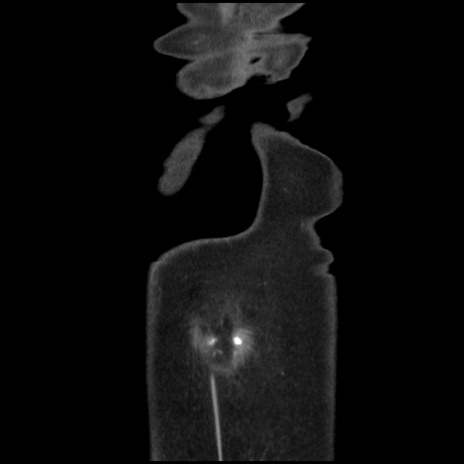

矢状断像